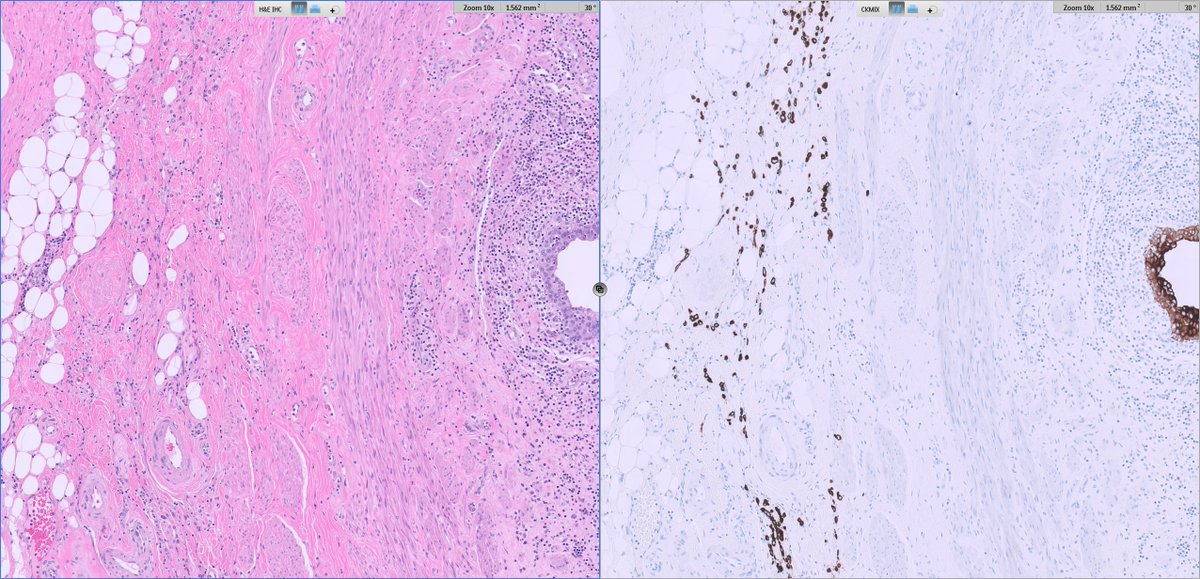

Architecture: grossly nodular tumors, but with infiltrative borders and “honeycomb” spread through subcutaneous fat and skeletal muscle.

Cytology: ovoid/epithelioid cells in cords, nests or solid sheets within dense collagenous stroma; mitotic activity usually low in hypocellular areas, higher in more solid/anaplastic foci.

Special patterns: perineurioma‑like areas (bland spindle cells in whorled/loose‑storiform pattern), fibroma‑like zones (very dense collagen with sparse cells), and foci of small round or rhabdoid cells in recurrences/metastases.

Perineurioma/DFSP – honeycomb infiltration and CD34 expression may overlap, but they lack SEF‑like morphology and YAP1–KMT2A fusion.

Fibromatosis/scar – fibroma‑like areas may mislead; subtle atypia, transition to more cellular SEF‑like zones, and EMA/cyclin D1 expression favor sarcoma.

📌Consider YAP1::KMT2A‑rearranged sarcoma in SEF‑like/LGFMS‑like tumors that are MUC4‑negative.

MUC4 negativity + EMA/cyclin D1 positivity and a YAP1–KMT2A fusion define the diagnosis.

📌Clinically, this is a malignant sarcoma with a real risk of lung metastasis, even when histology appears deceptively bland.